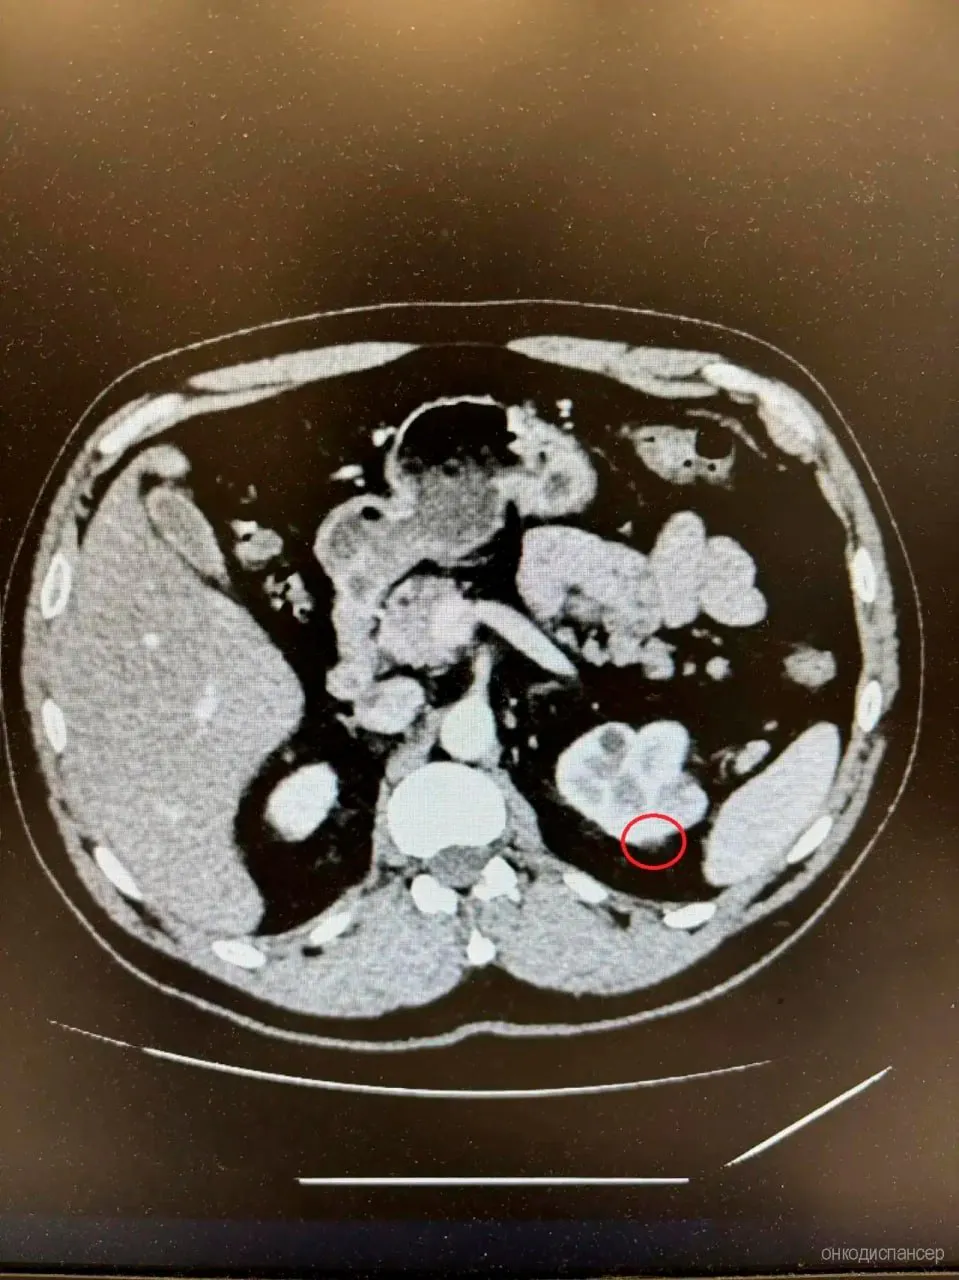

В рязанском онкодиспансере провели уникальную операцию. 48-летнему пациенту за один раз удалили злокачественные новообразования прямой кишки и левой почки, рассказали в пресс-службе учреждения.

Колоноскопия выявила опухоль прямой кишки, а дополнительное обследование — новообразование почки. Всё удалили одновременно. Операция прошла успешно. Уже на восьмые сутки пациента выписали в удовлетворительном состоянии.